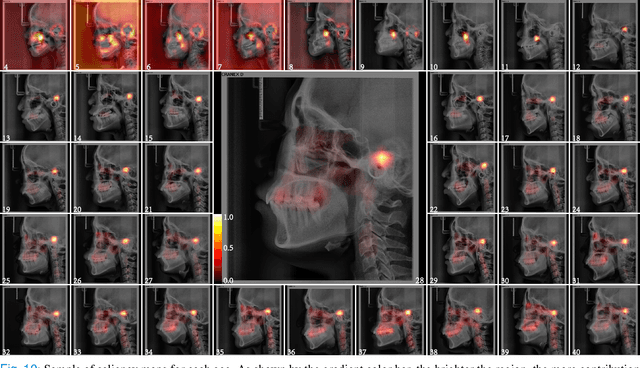

Abstract:The traditional manual age estimation method is crucial labor based on many kinds of the X-Ray image. Some current studies have shown that lateral cephalometric(LC) images can be used to estimate age. However, these methods are based on manually measuring some image features and making age estimates based on experience or scoring. Therefore, these methods are time-consuming and labor-intensive, and the effect will be affected by subjective opinions. In this work, we propose a saliency map-enhanced age estimation method, which can automatically perform age estimation based on LC images. Meanwhile, it can also show the importance of each region in the image for age estimation, which undoubtedly increases the method's Interpretability. Our method was tested on 3014 LC images from 4 to 40 years old. The MEA of the experimental result is 1.250, which is less than the result of the state-of-the-art benchmark because it performs significantly better in the age group with fewer data. Besides, our model is trained in each area with a high contribution to age estimation in LC images, so the effect of these different areas on the age estimation task was verified. Consequently, we conclude that the proposed saliency map enhancements chronological age estimation method of lateral cephalometric radiographs can work well in chronological age estimation task, especially when the amount of data is small. Besides, compared with traditional deep learning, our method is also interpretable.